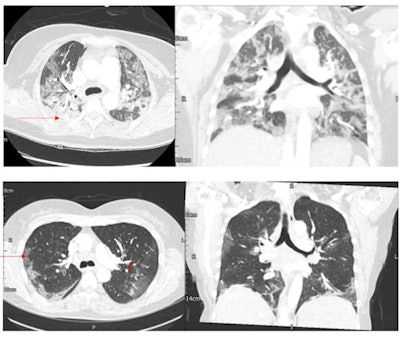

The SARS-CoV-2 omicron variant shows fewer and less severe changes on chest CT than its delta variant predecessor, but it does have at least one distinct manifestation -- bronchial wall thickening, research published on 21 June in Radiology has found.

"Bronchial wall thickening was more common with omicron than with delta SARS-CoV-2," the researchers noted.

Since there's not much research that evaluates the lung imaging findings of omicron compared with other SARS-CoV-2 variants, Tsakok and colleagues conducted a study to investigate whether the two variants show particular radiological patterns on chest CT. The research included data from 106 patients who tested positive for SARS-CoV-2 between December 2021 and January 2022. Of these, 66 contracted the delta variant and 40 contracted the omicron variant.

More of the individuals who contracted the omicron variant had normal results on CT pulmonary angiograms compared with those who had the delta variant, and those ill with omicron had CT severity scores lower by 7.2 points than those ill with delta.

The takeaway? Omicron causes less acute illness and fewer hospitalizations, but it does spread rapidly, and bronchial thickening is more than doubly common in patients with omicron than those with delta (odds ratio, 2.4 and 1, respectively), according to the authors.